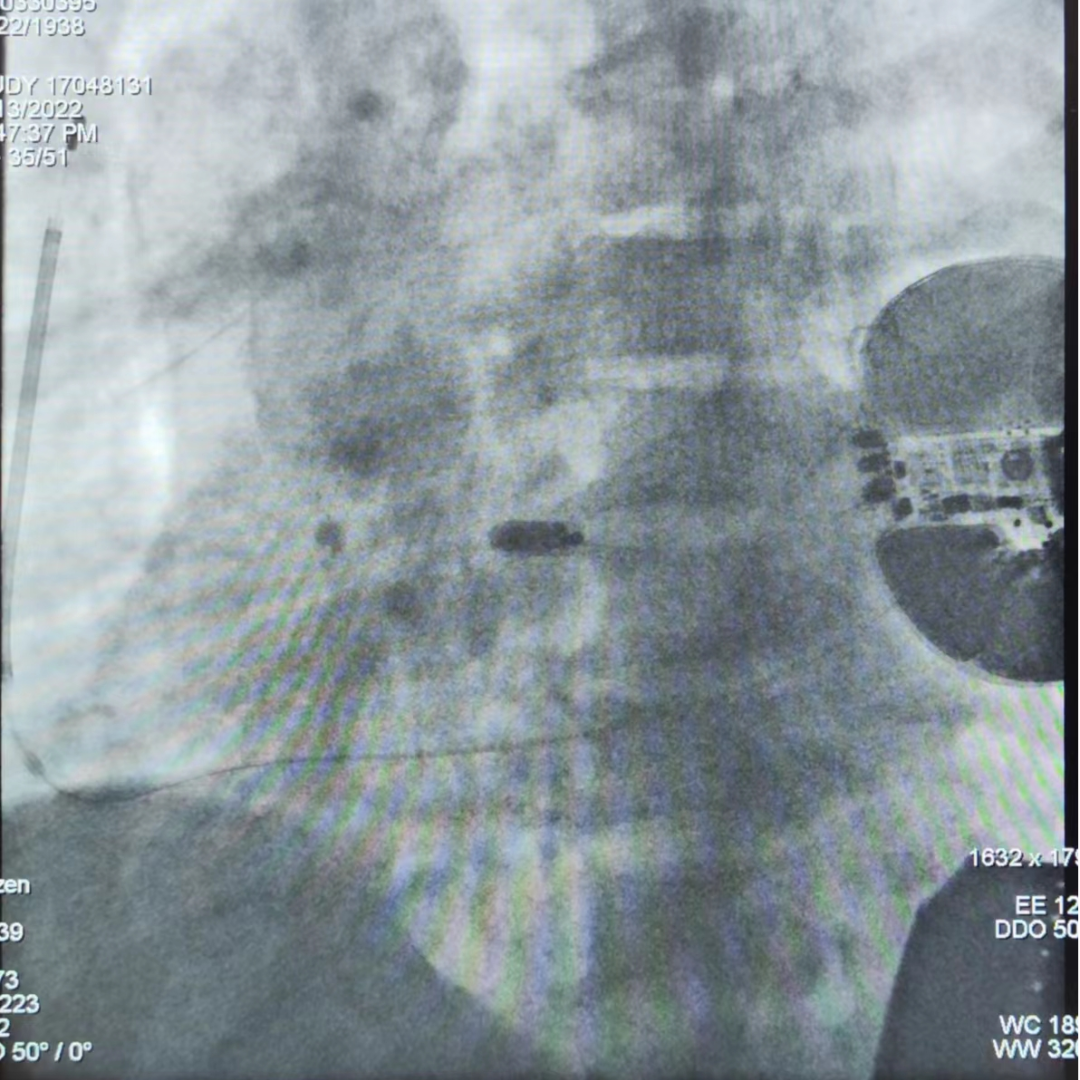

手术在全麻和深度镇静下进行,常规消毒、铺巾。取左腋中线第5-6肋为预定点,切开一约5cm的切口,逐层分离至皮下,分离囊袋至背阔肌与前锯肌之间。再次于剑突左上缘1cm为预定点,切开一长约2cm切口,逐层分离至深筋膜层,预埋两根缝合线,用导引针于切口间建立隧道,后引导除颤电极于皮下,固定除颤电极。用导引针导引除颤电极于深筋膜层至胸骨上窝位置,固定脉冲发生器于深筋膜层。进行除颤测试,采用50Hz,200mA交流电方式诱发室颤,SICD正确识别,经首次65J除颤成功,除颤阻抗74Ω,缝合皮肤,术区纱布覆盖,包扎,弹力绷带加压包扎止血。随后,通过股静脉穿刺,递送系统顺利定位室间隔,micra一次释放到位,成功将无导线起搏器通过导管植入到心腔内部,随之进行牵拉试验,验证了micra四个钩齿牢固地卡入心肌组织,通过不间断的心电系统检测,阈值0.38V,感知12.2mv,阻抗700Ω。整个手术过程顺利,仅耗时约2小时。

AP

LAO